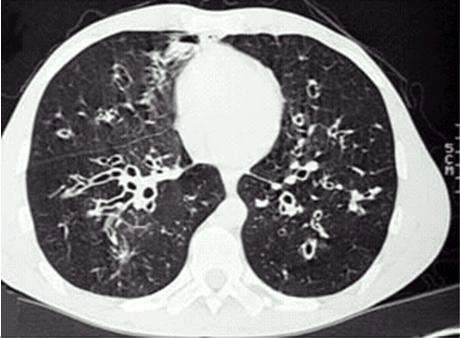

支气管扩张

当声带闭合时,下呼吸道处于密闭状态,气道内的血管破裂出血多属于病变所引起。因此,咯血多表明气管、支气管、肺等出现病变。常见原因有三种:肺结核、支气管扩张、肺癌。在我国,首要原因为肺结核,其次为支气管扩张和肺癌。年青人痰中带血,如伴有咳嗽、盗汗、消瘦等症状,多考虑结核;老年人则以肺癌可能性大,特别是出现刺激性咳嗽和有长期吸烟史者。如果是有咯脓痰史者,则以支气管扩张多见。另外,肺炎、支气管炎也有痰中带血的现象发生。慢性支气管炎和支原体肺炎也可出现痰中带血,但量一般较少。